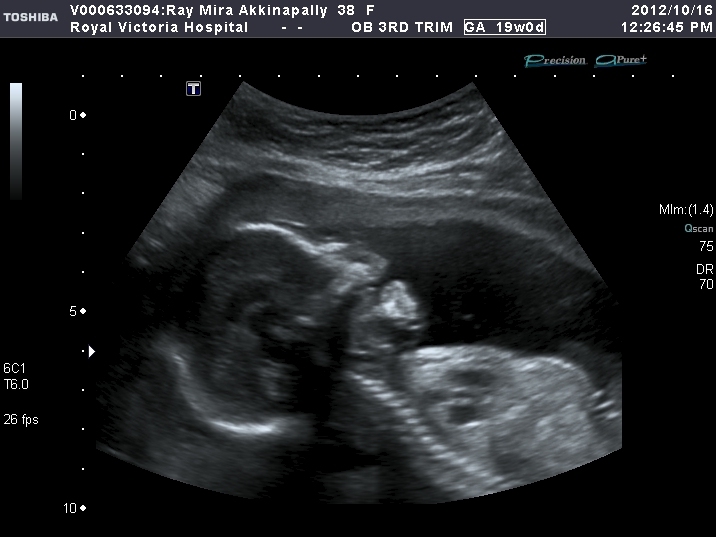

In this week's ultrasound (week 19) you can see she's getting bigger:

Here she is, caught in the act of:

Thinking

Yawning (life is so tough when your T-minus-21 weeks old)

...and practicing her best Halloween face